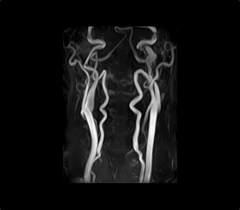

使用する医療機器と症例画像

- 東芝メディカルシステムズ社製

EXCELART Vantage1.5T

- 頭部MRA正面画像

- 頸部MRA正面画像